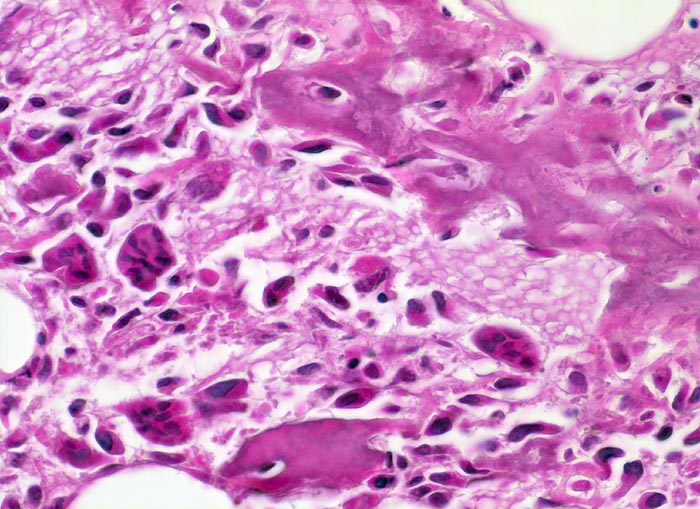

• Tibiametaphyse mit angrenzendem Weichteilgewebe.

• Das Sarkom infiltriert diffus den spongiösen Knochen der Diaphyse und hat präexistente Knochenbälkchen verdrängt.

• Der Tumor hat die Korticalis destruiert und infiltriert die angrenzende Skelettmuskulatur.

• Der Tumor besteht aus neugebildetem bereits verkalktem Knochen oder einem Netzwerk von primitiven Osteoidtrabekeln. Entlang oder innerhalb der Osteoidtrabekel lokalisierte polymorphe Tumorzellen mit ausgeprägten Kernatypien und zahlreichen Mitosen. Leicht verwaschene Kernstrukturen als Folge der Gewebsentkalkung.